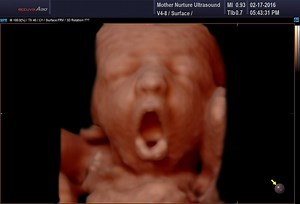

4:17

24K views · 342 reactions | Check out this amazing ultrasound compilation video featuring funny things babies do in the womb! | Mother Nurture Ultrasound | Facebook

Facebook

Mother Nurture Ultrasound

已浏览 2.5万 次

6 天之前